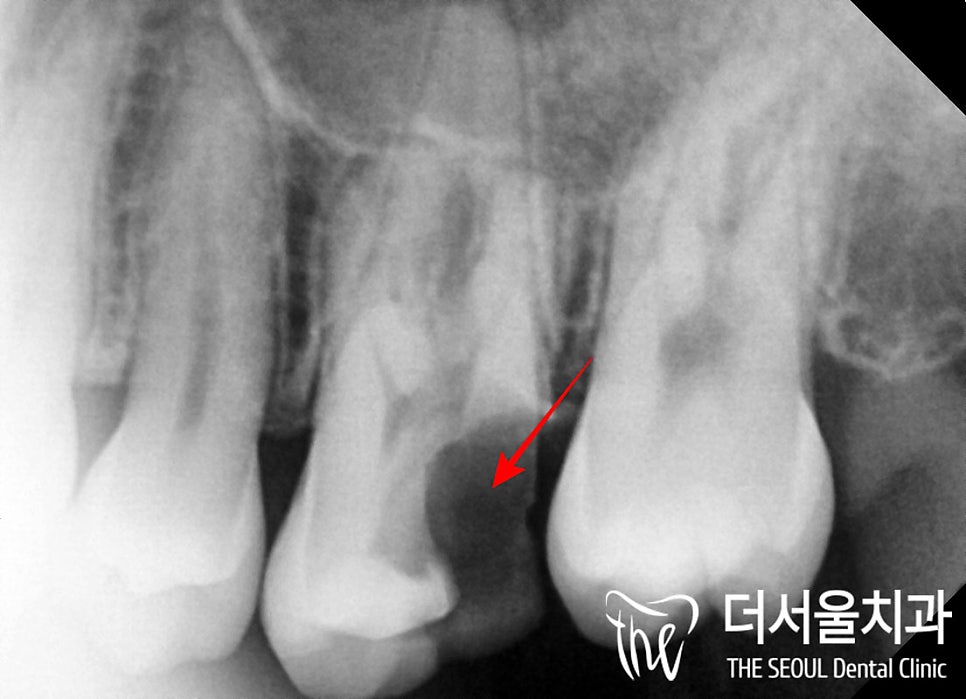

2. 정밀 진단

성남 치과 에서는

육안으로 1차 검사를 한 뒤,

엑스레이를 찍어

정확한 상태를 한 번 더 파악하는데요,

파노라마를 보면

예측했던 대로

심한 우식으로 인하여

주된 저작기능을 해야 되는

어금니들이 부러지고

깨져있습니다.

혹시 살릴 수 없을까

치근단 사진을 찍어보았으나

이미 치근분지부까지

우식 범위가 넓게 퍼져있었으며

부러진 이들은

치조골 내에서

염증을 일으키며

뼈를 녹이고 있었습니다.